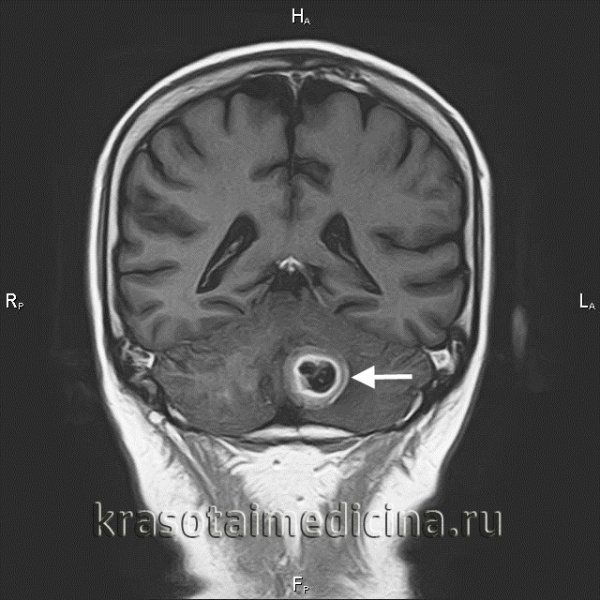

(Слева) При КТ височной кости у младенца с правосторонним параличом ЧН VII определяется литическая, пермеативная деструкция вершины пирамиды; плотная костная слуховая капсула интактна. Опухоль распространяется в полость среднего уха и обусловливает эрозию передней стенки яремного отверстия.

(Справа) При аксиальной MPT Т2 ВИ FS у этого же пациента определяется гипоинтенсивное образование вершины пирамиды, сопоставимое с целлюлярной опухолью, распространяющейся в правый ВСК и мосто-мозжечковый угол. При биопсии подтвердилась нейробластома. При последующих исследованиях обнаружилась первичная опухоль надпочечника.